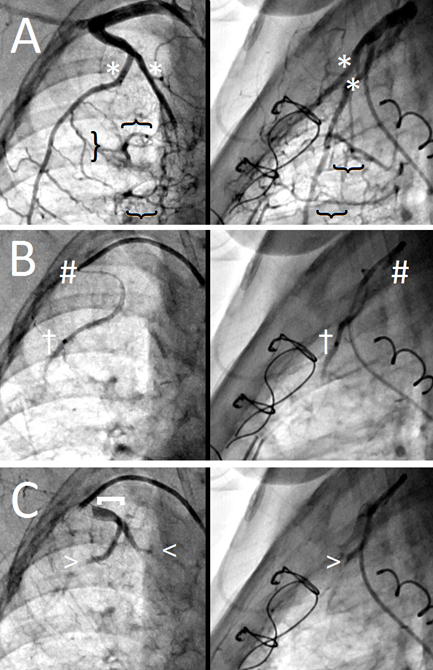

Figure 3: Occlusion of "complex" systemic-to-pulmonary collaterals.

(a) Note the two large branches (*) of the internal mammary artery (IMA) that give rise to multiple SPC networks (}).

(b) The two large feeding branches are individually engaged with the microcatheter for selective particle delivery (†); the guiding catheter tip remains ~1-2cm in the IMA as a landmark (#).

(c) Post-particle injection shows no residual SPC flow (arrowheads) with a patent IMA origin ([)